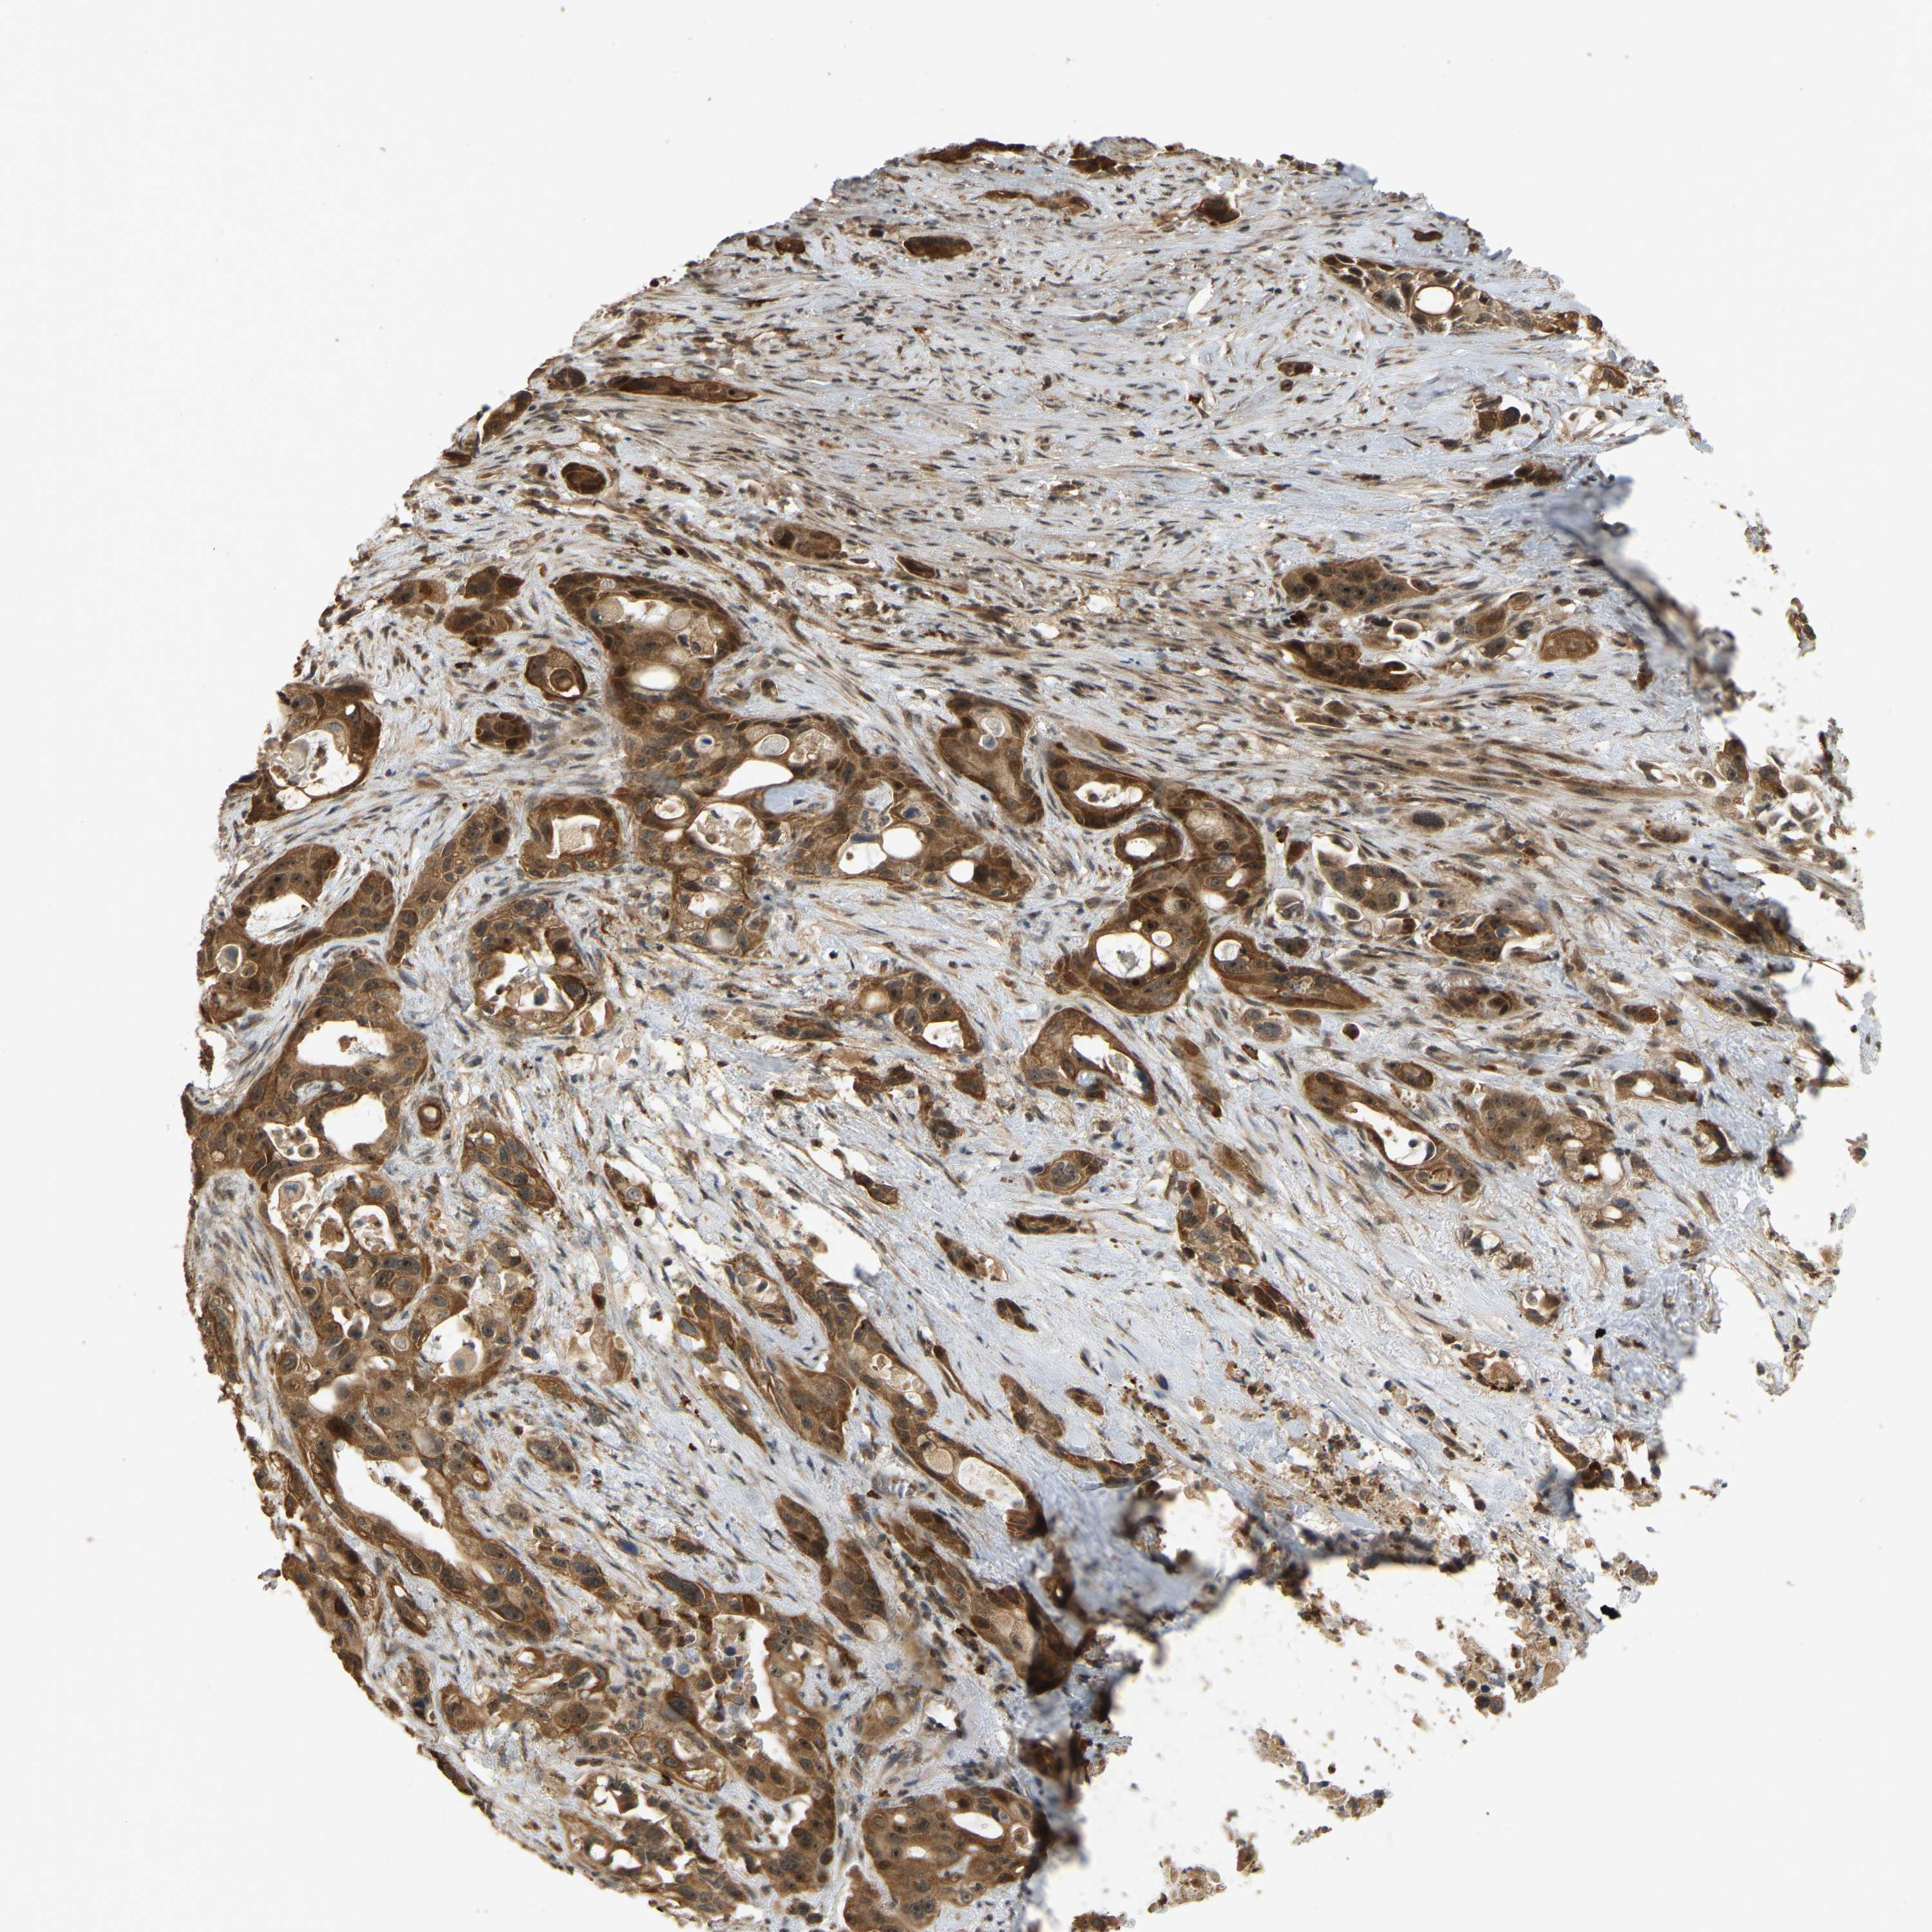

PANCREATIC CANCER - Protein expressioni

A mouse-over function shows sample information and annotation data. Click on an image to view it in a full screen mode. Samples can be filtered based on level of antibody staining by selecting one or several of the following categories: high, medium, low and not detected. The assay and annotation is described here.

Note that samples used for immunohistochemistry by the Human Protein Atlas do not correspond to samples in the TCGA dataset.

Antibody stainingi

Antibody staining in the annotated cell types in the current human tissue is reported as not detected, low, medium, or high, based on conventional immunohistochemistry profiling in selected tissues. This score is based on the combination of the staining intensity and fraction of stained cells.

Each image is clickable and will lead to virtual microscopy that enables deeper exploration of all samples and also displays staining intensity scores, fraction scores and subcellular localization as well as patient and tissue information for each sample.

Antibody HPA023378

Antibody CAB019269

Staining

High

Medium

Low

Not detected

Intensity

Strong

Moderate

Weak

Negative

Quantity

>75%

75%-25%

<25%

None

Location

Nuclear

Cytoplasmic/membranous

Cytoplasmic/membranous,nuclear

Adenocarcinoma, NOS

Adenocarcinoma, metastatic, NOS